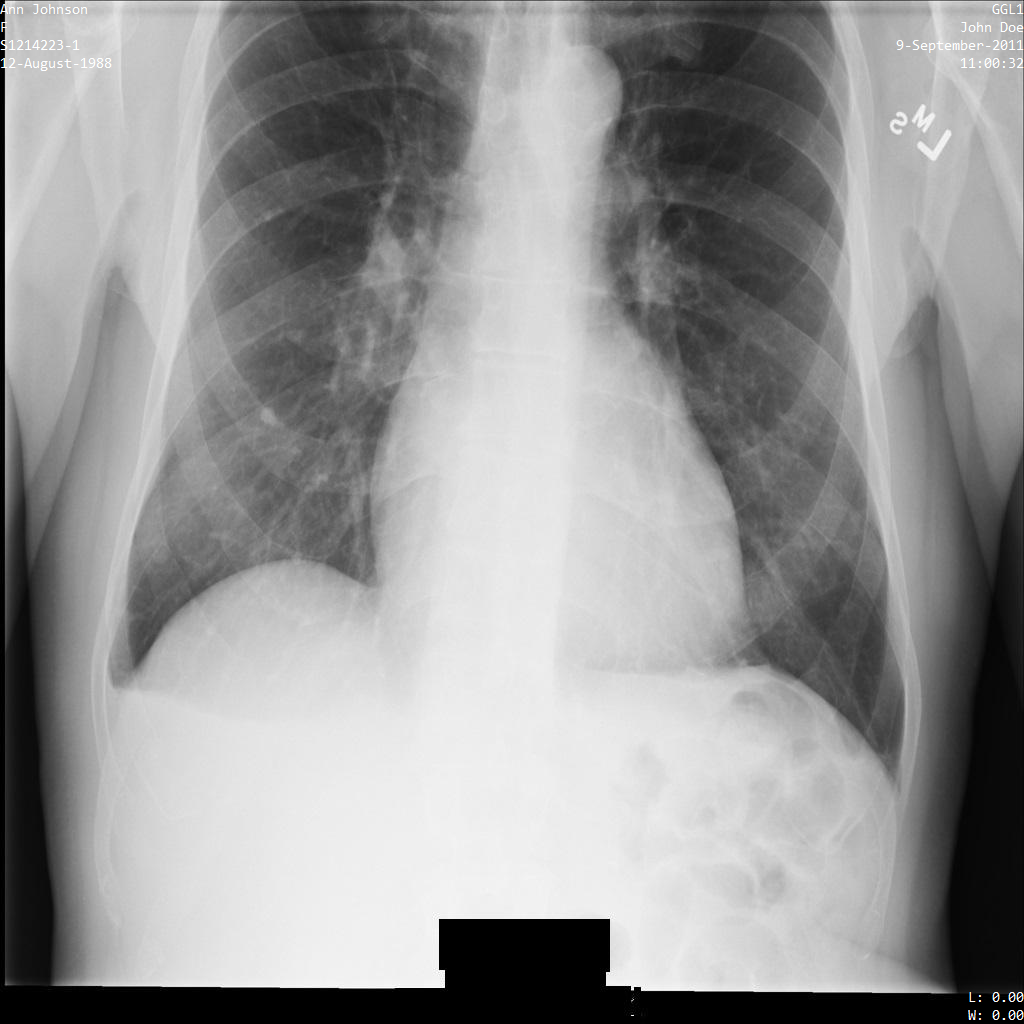

En cada una de las siguientes secciones, se proporcionan ejemplos de cómo desidentificar datos de DICOM mediante varios métodos. Se proporciona un resultado de la imagen desidentificada en cada muestra. En cada muestra, se usa la siguiente imagen original como su entrada:

Puedes comparar la imagen de salida de cada operación de desidentificación con esta imagen original para ver los efectos de la operación.